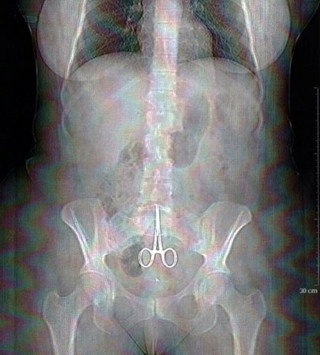

Ακτινογραφίες που σοκάρουν!

Όταν η επιστήμη σηκώνει τα χέρια ψηλά